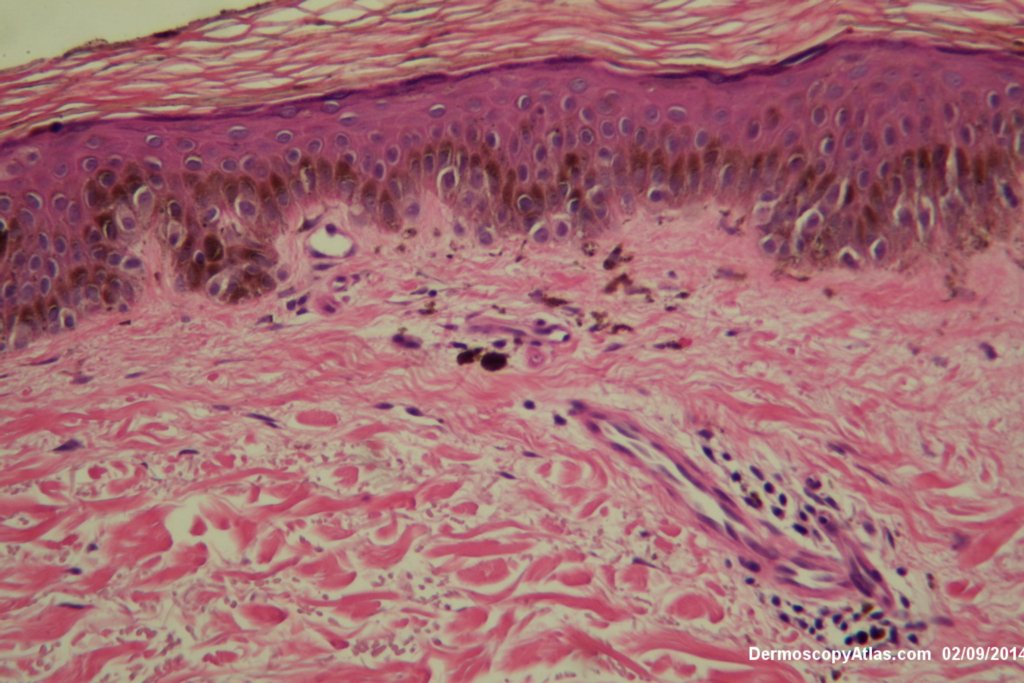

Image Number #3363 (Melanoma in situ)

Diagnosis: Melanoma in situ

Description: Pigmented macule at the ankle

This man has had a previous melanoma many years ago. This lesion had been present for two years on the akle but was considered chaotic under the dermatoscope and excised. It was reported as a melanoma in situ. Special stains were uised to show upward spread of melanocytes.

See the video to view a discussion of the pathology.